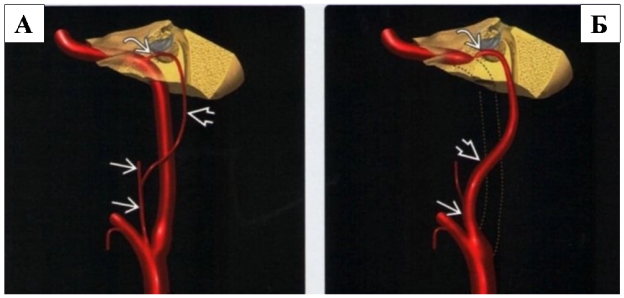

Рис. 2

На рисунке 2А в боковой проекции представлена нормальная внутренней сонной артерии (шейный и каменистый отделы ВСА), а также нижняя барабанная артерия, которая отходит от восходящей глоточной артерии, проходит в височную кость и анастомозирует с очень мелкой сонно-барабанной артерией в области мыса улитки.

На рисунке 2Б в боковой проекции пунктирными линиями представлены аномалии развития шейного отдела внутренней сонной артерии (ВСА). В норме кровоснабжение осуществляется альтернативными коллатералями: восходящей глоточной, нижней барабанной и сонно-барабанной артериями. Указанные особенности характерны для аберрантной внутренней сонной артерии (АбВСА).